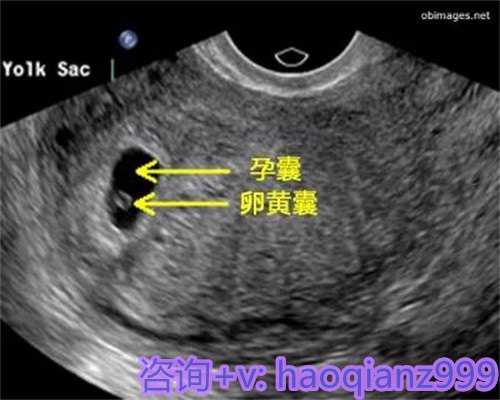

经过挑选后,供卵者须要进行取卵手术,这个历程须要在专业医师的指导下进行。医师会经过超声波引导,将针头刺进卵巢,抽取卵子。